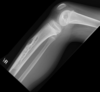

Fratura do platô tibial lateral - Schatzker tipo 2 (traço de fratura + depressão do plato lateral).